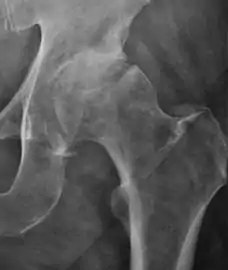

Plain radiography allows us to categorize the hip as normal or dysplastic or with impingement signs (pincer, cam, or a combination of both). Besides these, pathologic processes like osteoarthritis, inflammatory diseases, infection, or tumors can also be identified (Figure 1).[1]

Figure 1.

X-ray of cam